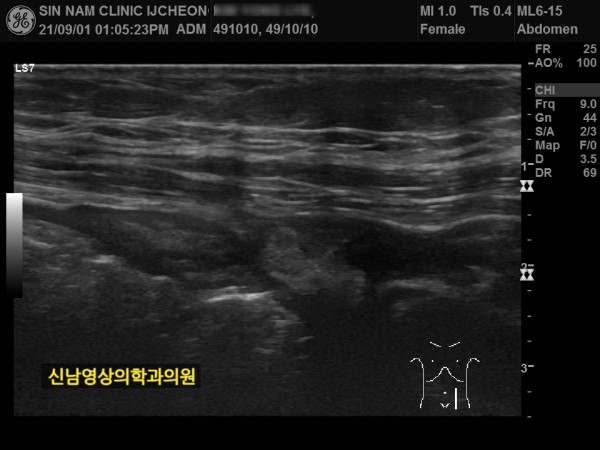

본 환자분께서는 사흘 정도 지속되는 복통과 고열로 내원하신 60대 중반의 환자분입니다.

복통 부위의 병변을 확인하기 위해서 복부 촬영과 복부 초음파검사를 진행했고, 맹장은 이상이 없고, 대장 주위로 복강삼출액(물)이 둘러싸고 있으면서 상행대장부위의 부종이 심하게 발견되었습니다.

상복부 초음파 검사는 간, 담낭, 담관, 췌장, 신장, 비장 등 상복부 주요 장기를 초음파로 실시간 영상화해 진단하는 검사입니다.

구조와 이상有無를 확인합니다.

지방간, 간염, 간경변, 간암, 담석증, 담낭염, 췌장염, 신장 결석, 종양 등 다양한 질환을 진단할 수 있습니다.

일상에서의 복부 통증, 소화불량, 체중 감소, 복부 종괴가 있을 때 시행합니다.